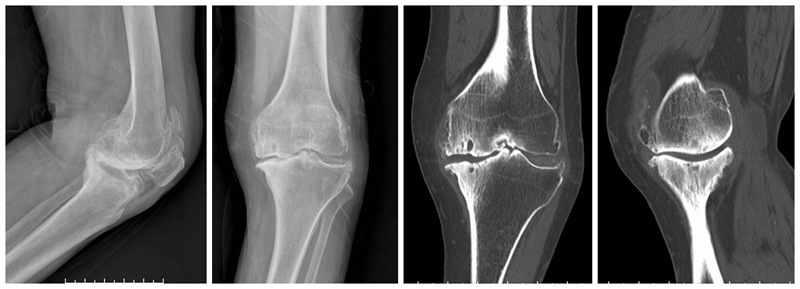

内侧单髁置换术(非骨水泥型)

术前

术后检查

膝关节单髁置换术后的翻修率的一个主要原因是无菌性假体松动。临床上常常用术后X线平片上是否出现透亮带来判定假体是否松动。事实上部分骨水泥型单髁假体,术后x线片常常可见生理性透亮带,容易误诊为假体松动,从而导致不必要的术后翻修,生物型单髁置换假体的推广减少了单髁翻修率,延长了假体的使用寿命。

现阶段生物型单髁假体也逐步被越来越多医生与患者选择。对于生物型假体,需要注意以下几点:(1)垂直截骨开槽避免用常规骨水泥型假体工具,以免开槽过宽导致假体置入松动。(2)开槽过程中需要特别谨慎小心,敲击力度适宜,以防胫骨劈裂骨折。(3)年龄大,骨质疏松明显以及股骨髁坏死病例用生物型假体应更加慎重。

合并ACLD的单髁置换术

ACL损伤是否适合单髁置换,争议较大。需要鉴别原发韧带损伤继发OA还是原发OA继发ACL损伤。前者一般年龄轻,运动量大,适合一期或二期UKA联合ACL重建,后者一般年龄偏大,运动量少,需要术前详细评估膝关节稳定性。UKA仍是治疗内外不稳定的一种选择,而前后不稳定应探索其他治疗方案。髁间窝骨赘作为膝关节二级静态稳定结构。手术中引起撞击或磨损的骨赘要完全去除,其它骨赘建议保留。必须保留所有残留的ACL。适度减少胫骨后倾,一般应小于5°。